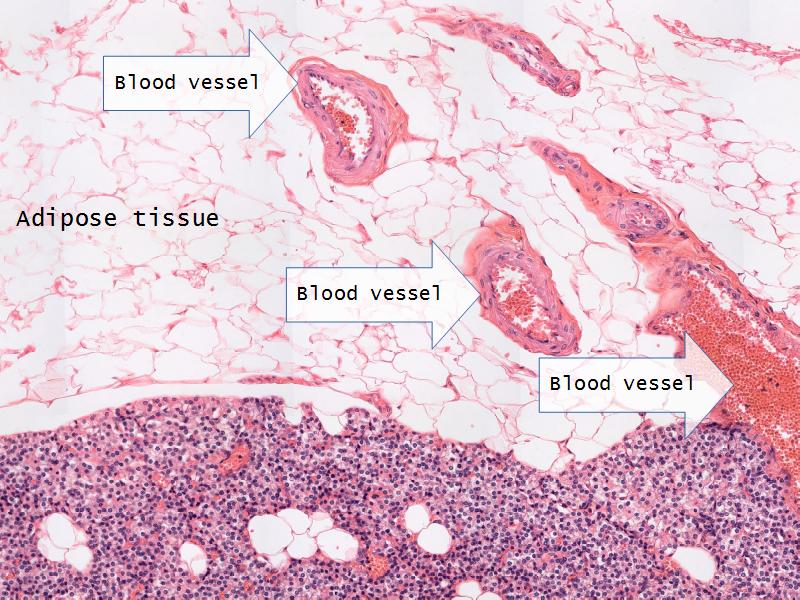

- Parathyroid glands

- Slide 54: Parathyroid glands

Chief cells = majority

Oxyphil (acidophil) = single/groups